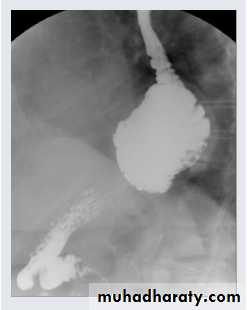

PA chest X-ray: A smooth-contoured cavity of 5 cm diameter, containing gas fluid level, is visible behind the heart shadow (arrow). This lesion is the gas-containing fornix protruding into the chest cavity through the esophageal hiatus.

chest practice

A barium swallow study demonstrates a large hiatal hernia with the majority of the stomach in the chest, not in the abdomen where it belongs.